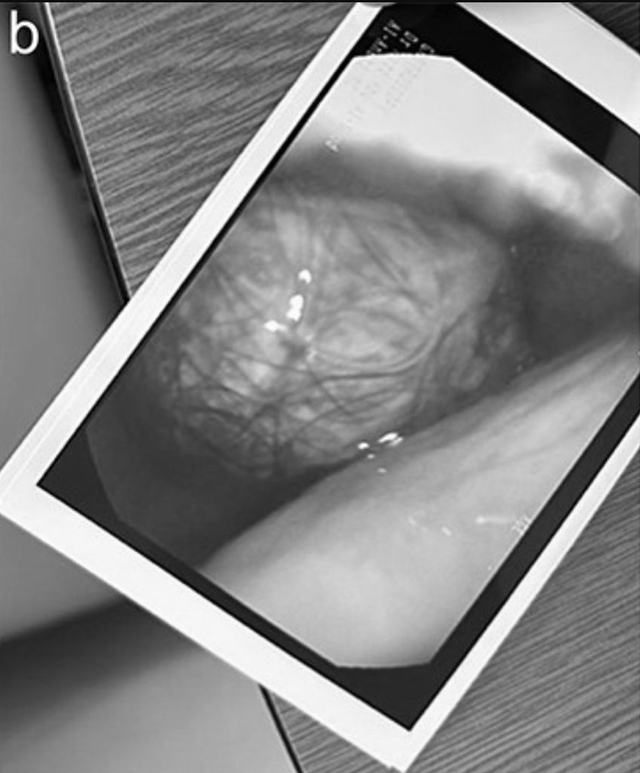

Trong khi tất cả các xét nghiệm trong phòng thí nghiệm đều bình thường, kết quả chụp CT xác nhận rằng búi tóc khổng lồ đã kéo dài từ dạ dày đến tá tràng.